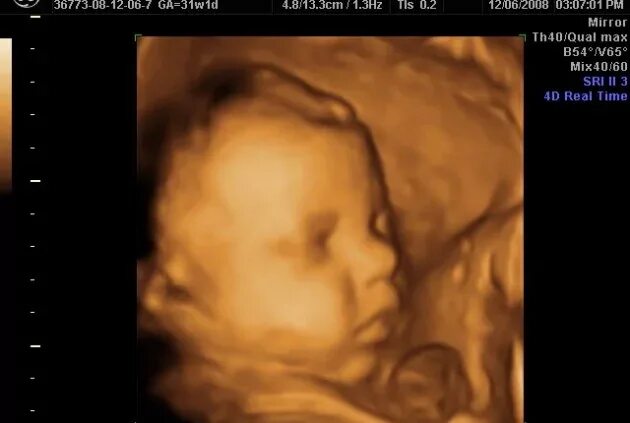

Ребенок 36 недель беременности в животе